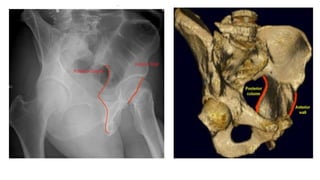

Acetabular fractures

● Anatomy

○ Supported by two columns

○ Anterior column

■ Anterior ilium,anterior wall and dome, iliopectineal eminence, superior pubic rami

○ Posterior column

■ Quadrilateral plate, posterior wall and dome, ischial tuberosity, greater and lesser sciatic

● Imaging

○ AP

■ Six radiographic landmarks

■ Dome, anterior wall, posterior wall, iliopectineal line, ilioischial line

○ judet( oblique) views

■ Obturator oblique - anterior column and posterior wall

■ Iliac oblique- posterior column and anterior wall

● Anatomy ○ Acetabularcap ■ 40-48 deg lateral inclination , 18-21 degree anteversion ○ Supported by two columns ○ Anterior column ■ Anterior ilium,anterior wall and dome, iliopectineal eminence, superior pubic rami ○ Posterior column ■ Quadrilateral plate, posterior wall and dome, ischial tuberosity, greater and lesser sciatic notch

● Imaging ○ AP ■Six radiographic landmarks ■ Dome, anterior wall, posterior wall, iliopectineal line, ilioischial line ○ judet( oblique) views ■ Obturator oblique - anterior column and posterior wall ■ Iliac oblique- posterior column and anterior wall